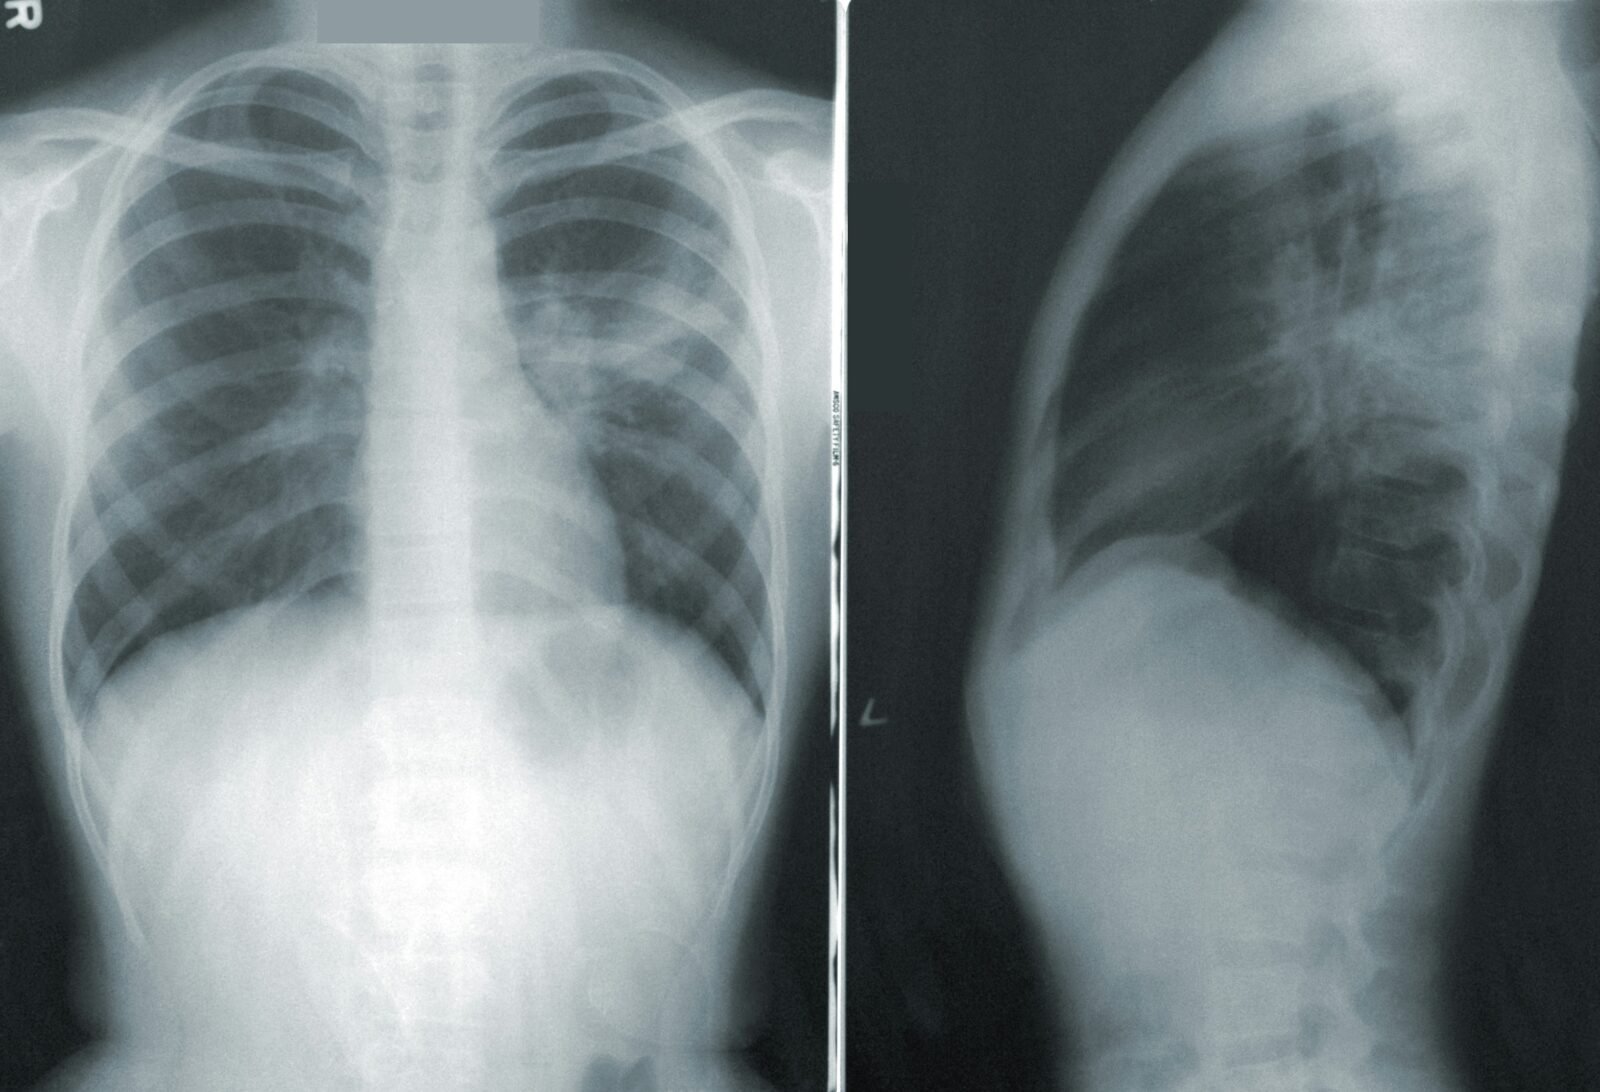

Embora a avaliação clínica seja fundamental, em alguns casos, podem ser necessários exames complementares para confirmar o diagnóstico ou avaliar a gravidade da condição. Alguns dos exames que podem ser realizados incluem:

- Radiografia de tórax

| Radiografia de tórax | Avaliar a presença de pneumonia ou outras complicações |